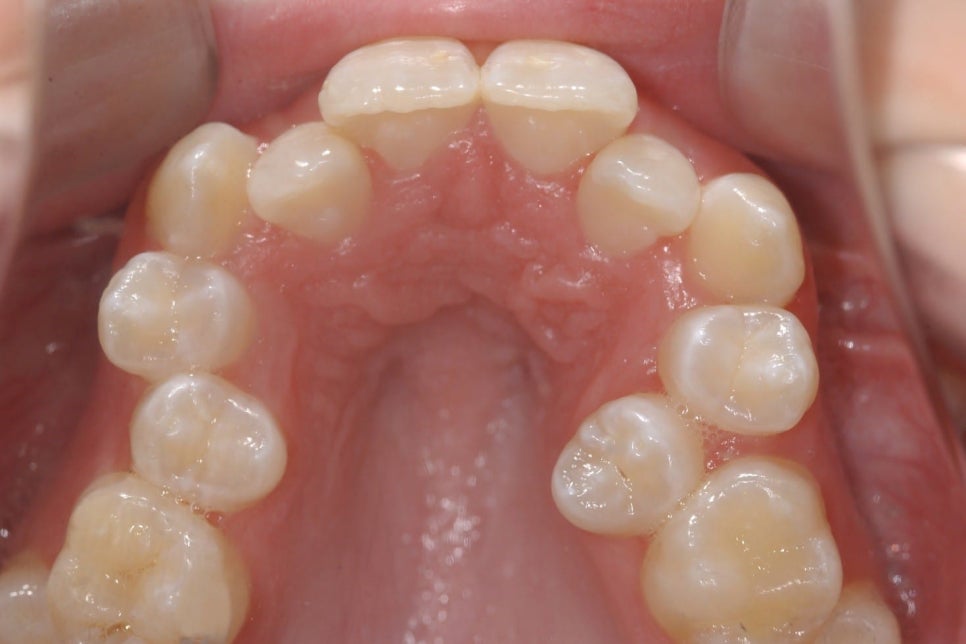

치아교정은 치아를 가지런히 배열하기 위해 진행하는 것입니다. 하지만 공간이 없다면요? 위 사진의 경우 도저히 발치를 하지 않고서는 충분한 공간 확보가 어려워보입니다. (출처: https://www.forbesorthodontics.com/)